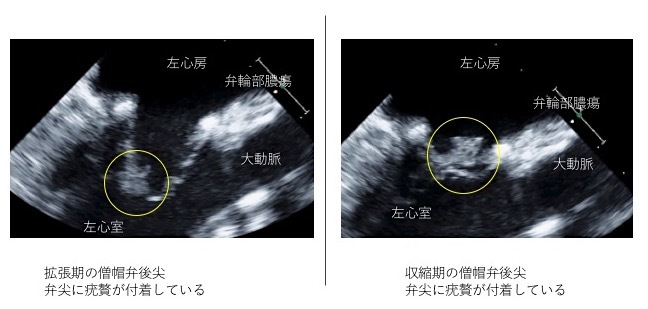

また、感染源が心臓であるかどうかを調べるために、心臓超音波検査を行います。感染性心内膜炎を発症している場合、心臓超音波検査を行うと疣贅の付着が確認できます。

また、患者さんのなかには弁輪部(弁の外周部分)に感染及び膿瘍を形成していることがあります。その場合には、弁輪部の膿瘍を切除したうえで、弁輪部の形を整える難易度の高い手術が必要になります。